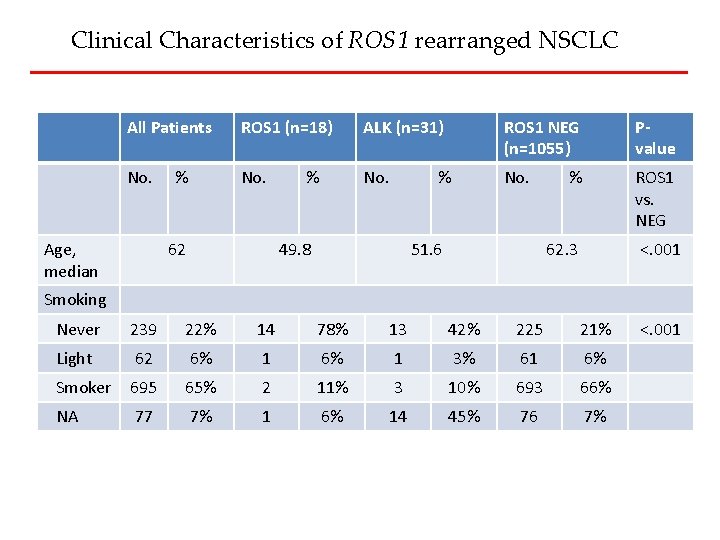

Clinical Characteristics of ROS 1 rearranged NSCLC All Patients ROS 1 (n=18) ALK (n=31) ROS 1 NEG (n=1055) Pvalue No. ROS 1 vs. NEG Age, median % 62 % % 49. 8 51. 6 % 62. 3 <. 001 Smoking Never 239 22% 14 78% 13 42% 225 21% Light 62 6% 1 3% 61 6% Smoker 695 65% 2 11% 3 10% 693 66% NA 77 7% 1 6% 14 45% 76 7% <. 001